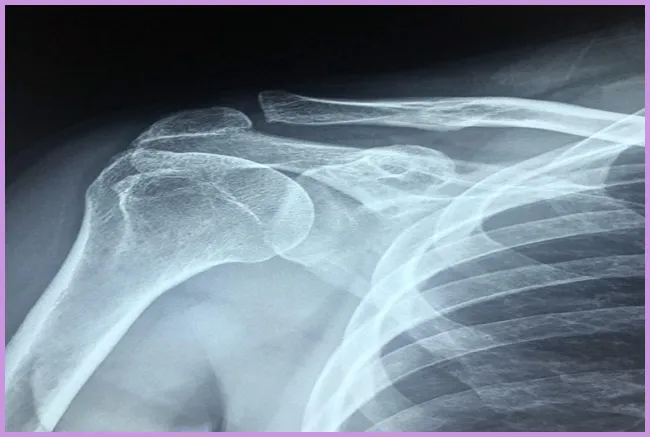

어깨 충돌증후군에 대한 이해는 많은 사람들에게 필수적입니다. 이 증후군은 어깨 통증을 유발하고, 일상생활에서의 불편함을 초래할 수 있습니다. 치료법, 원인, 운동법을 함께 살펴보며, 이 증후군을 어떻게 효과적으로 관리할 수 있는지 알아보겠습니다. 많은 사람이 이 문제로 고통받고 있지만, 적절한 예방 요법과 운동법을 통해 건강한 어깨를 되찾는 데 도움을 줄 수 있습니다.

어깨 충돌증후군이란 무엇인가?

어깨 충돌증후군은 어깨의 움직임이 제한되는 상태로, 어깨 패드와 같은 구조물이 신경이나 힘줄과 충돌하여 발생합니다. 특히 팔을 올리거나 회전할 때 통증을 느끼는 경우가 많습니다. 이 증후군은 특히 운동선수나 반복적으로 어깨를 사용하는 직업에서 흔하게 발생합니다.